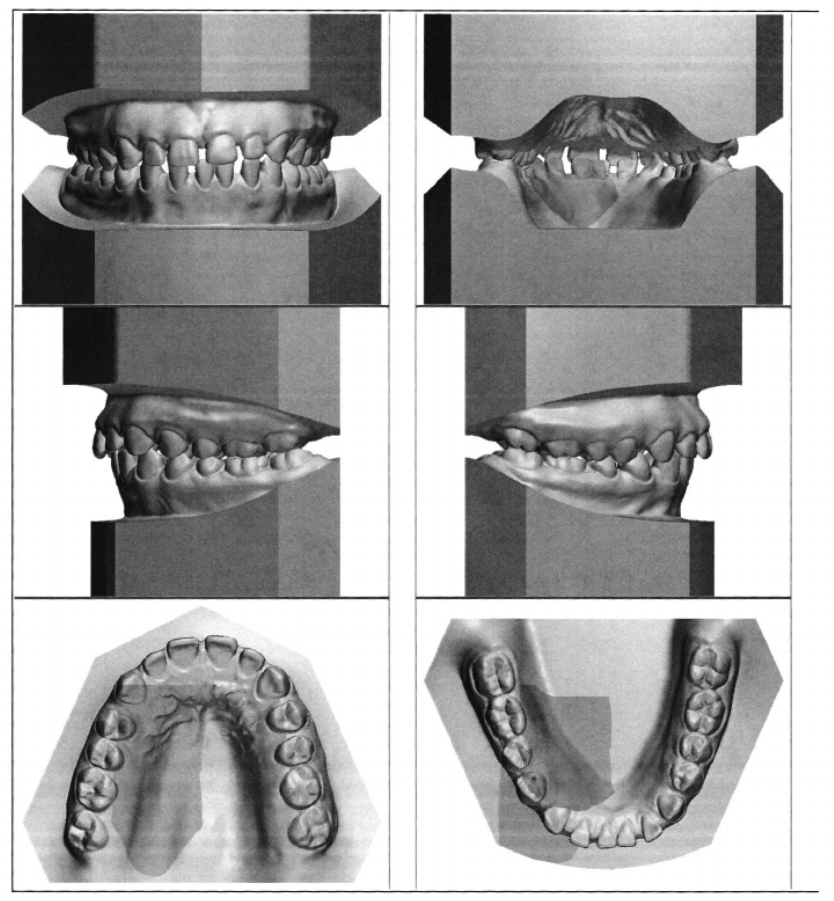

Qualifying criteria for the requested orthodontic service should be shown clearly in the photos (see example photos below, on page 2). The photos of the plaster, stone, or resin (3D printed) models should include the following views:

- Frontal Occluded

- Palatal Occluded

- Left Occluded

- Right Occluded

- Maxillary Occlusal

- Mandibular Occlusal

Example Model Photos: